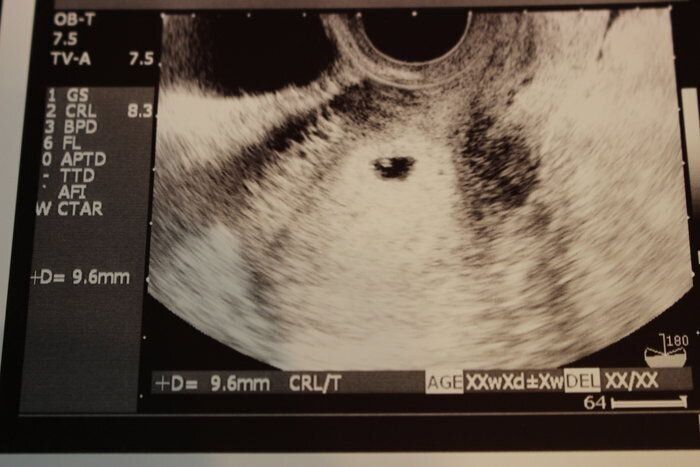

セイコさんの妊娠5週目のエコー写真 胎嚢が見えました!

妊娠しているみたいだけど、ちゃんと妊娠できているか祈る思いで病院を受診しました。人生はじめてのエコー写真です。この時点で妊娠5週目。「胎嚢が見えますね」と言われたときの喜びが忘れられません。